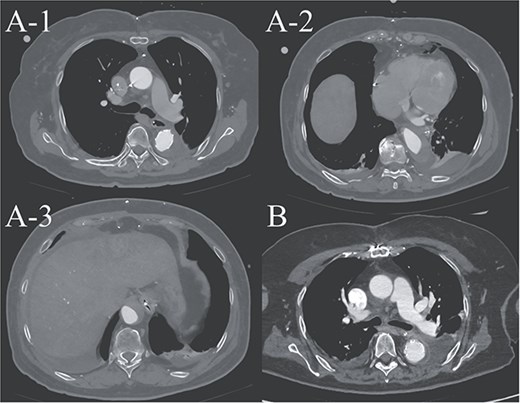

(A-1–3) contrast-enhanced CT image acquired on postoperative Day 2, showing advanced false lumen thrombosis. (B) Contrast-enhanced CT image acquired on postoperative Day 21, demonstrating further remodeling of the false lumen. This image is at approximately the same level as A-1, and the false lumen's thickness is clearly reduced.

A 70-year-old woman presented to the emergency department with sudden-onset chest and back pain. Contrast-enhanced CT revealed an ATAAD extending from the ascending aorta to the bilateral common iliac arteries. The primary entry tear extended from the ascending aorta into the aortic arch, and the false lumen remained patent throughout its entire peripheral extent (Fig. 1). Both renal arteries originated from the true lumen, and there was no malperfusion. Vital signs were stable, and the patient was not in shock. The patient underwent emergency total arch replacement with FET implantation using a 27 × 90 mm FROZENIX four-branched graft (Japan Lifeline Co., Ltd, Tokyo, Japan). The procedure was completed in 7 h and 6 min without intraoperative complications. Postoperatively, urine output declined markedly. Serum creatinine increased from a baseline of 0.81 to 2.61 mg/dl on postoperative Day 1. Diuretics failed to improve urine output, and renal replacement therapy was initiated. Contrast-enhanced CT on postoperative Day 2 showed no signs of renal malperfusion. Although the renal medulla exhibited normal enhancement, a diffuse non-enhancing area throughout the renal cortex—referred to as the “reverse rim sign”—was observed, consistent with RCN (Fig. 2). Thrombosis of the false lumen in the descending thoracic and thoracoabdominal aorta had progressed (Fig. 3). The patient developed persistent coagulopathy, with sustained hypofibrinogenemia and thrombocytopenia. On postoperative Day 2, the platelet count was 4.1 × 104/μl, D-dimer 13.5 μg/ml, and PT-INR 1.54, yielding an International Society on Thrombosis and Hemostasis DIC score of 6, consistent with overt DIC. Anticoagulation therapy with heparin and warfarin was administered. Ultimately, by postoperative Day 50, a total of 36 units of fresh frozen plasma and 100 units of platelets had been transfused; however, coagulation parameters gradually normalized thereafter, and no further transfusions were required (Fig. 4). A follow-up CT on postoperative Day 21 demonstrated further remodeling of the thrombosed false lumen. Brain magnetic resonance imaging performed on postoperative Day 9 to investigate delayed emergence revealed multiple scattered small acute ischemic infarctions involving the cerebellum, brainstem, and cerebral cortex (Fig. 5). These were not attributed to large-vessel occlusion but rather to systemic microthrombotic emboli. Despite supportive care, renal function did not recover, and maintenance dialysis was initiated. The patient was transferred to another hospital on postoperative Day 182.